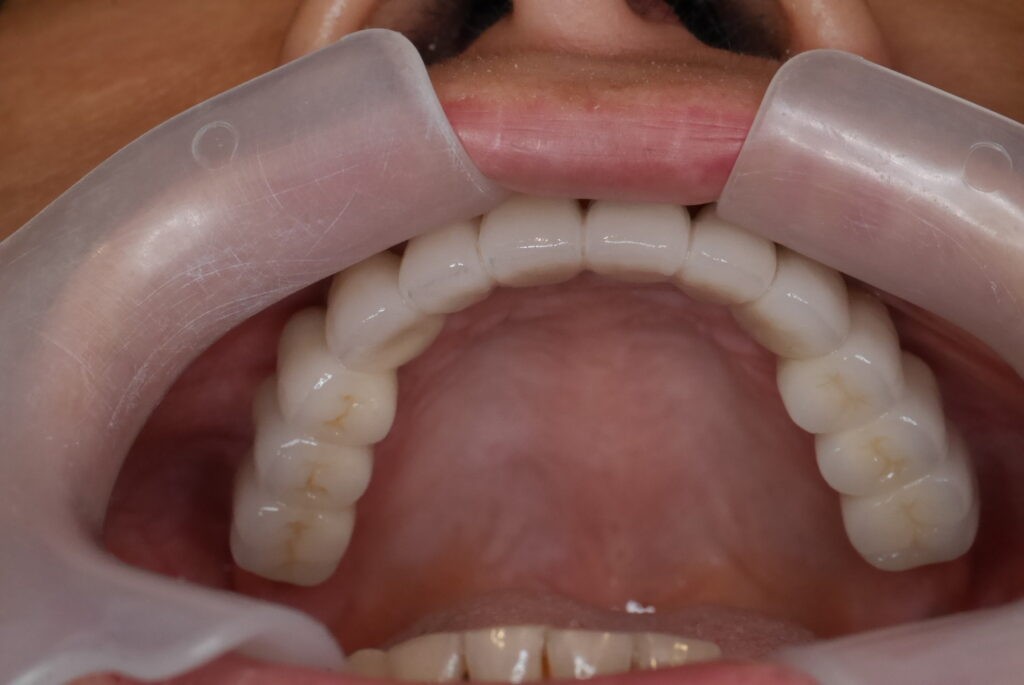

殘根拔除後,植入6支人工牙根

數位取模,置入植體掃描桿

數位取模 德國口掃機 口內精準掃描

數位取模 電腦設計 電腦製作

假牙完成